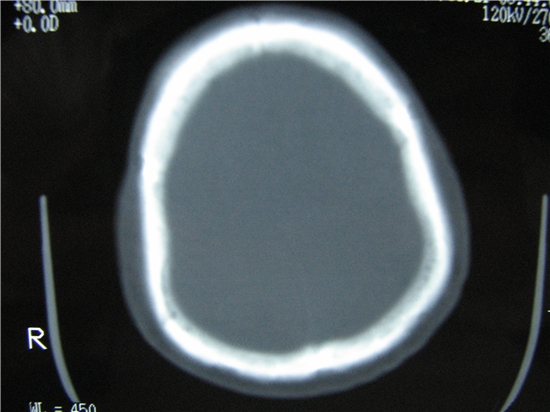

标题: CT23231:男 32岁 车祸伤,鼻腔内出血明显。 [打印本页]

标题: CT23231:男 32岁 车祸伤,鼻腔内出血明显。

额窦内及额部软组织内可见多发游离类骨质密度影,考虑额骨骨折可能。

额窦致密骨瘤,前额部及右顶部头皮损伤伴异物存留

左侧额骨、鼻骨骨折,头面部软组织肿胀。

左侧额骨、鼻骨骨折,额窦内的应该是游离骨块